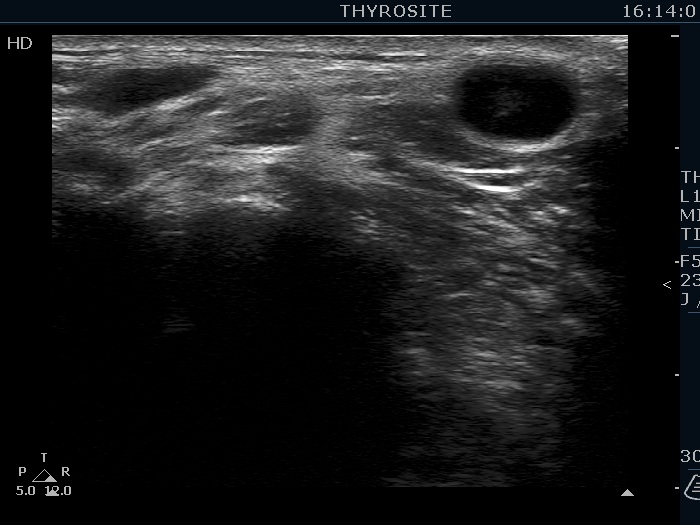

Ultrasonography. The thyroid was echonormal. There were several hypoechoic nodules in the left lobe. The middle one had back wall cystic figures. There were 3 or four discrete, deeply hypoechoic lesions above and lateral to the left lobe in the neck. One of them presented with a hilum-like figure while the others lacked hilum.

The lymph nodes had a non-typical presentation. They lacked a regular hilum.